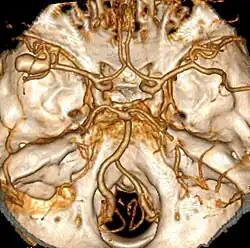

Angiografie

Die zerebrale Angiografie wird als Standardmethode geführt; sie ist ein an Kontrastmittel gebundenes Verfahren der Gefäßdarstellung unter Einsatz von Röntgenstrahlung. Bei hoher Sensitivität muss sie aber in den ersten Stunden durchgeführt werden, da anschließend das Aneurysma als Blutungsquelle verschlossen werden muss, um einen therapeutischen Nutzen zu erlangen. Diese seit langem ausgereifte Methode gilt in ihrer Sonderform, der digitalen Subtraktionsangiografie, den virtuellen Gefäßdarstellungsverfahren von Computertomografie und Kernspin in der diagnostischen Aussagekraft derzeit noch überlegen. Letztere sind jedoch meist schneller erhältlich und für den Patienten weniger belastend.

Hauptsächlich sind Gefäße betroffen, die den Circulus arteriosus cerebri (Willis) bilden. Dieses Gefäßsystem an der Gehirnbasis verbindet die größten hirnversorgenden Arterien miteinander.

Rupturen (Einrisse) von Aneurysmen der Hirnbasis sind bei 80 % der Erkrankungen Ursache der Subarachnoidalblutung; außerdem kommen Angiome (gutartige Gefäßmissbildungen) und arteriovenöse Fehlbildungen vor. In 5–10 % aller Fälle kann keine Blutungsquelle gefunden werden.[7]